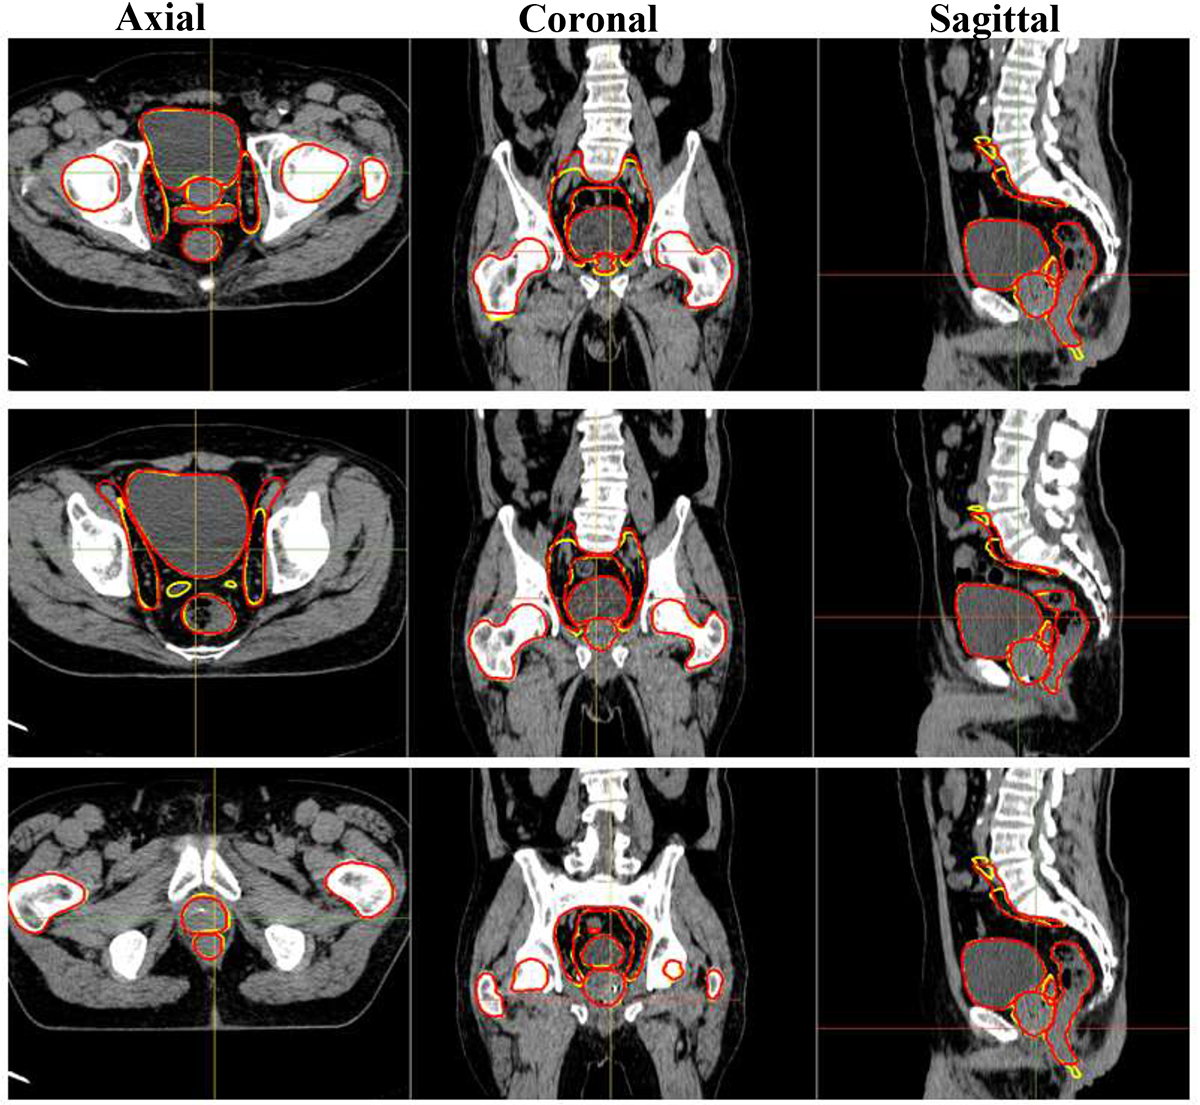

The segmentation using the 3D nnU-net took an average of 100 s per input volume on the standard PC with a GeForce GTX 8 GB NVIDIA and 32 GB RAM. Figure 2 represents manually delineated contours as ground truth and automatically generated delineations of the prostate, seminal vesicle, lymph nodes, femoral heads, rectum, and bladder for three test patients. The comparison of organ volumes delineated by radiation oncologists as the ground truth and automatic segmentation based on our proposed deep CNN method is presented in Table 1. It is obvious that the volumes defined by the nnU-net model are similar to the volumes defined by manual segmentation as the standard ground truth. Table 1 shows a statistically significant difference in seminal vesicle volumes between manual and automatic delineation.

Figure 2. Axial, coronal, and sagittal slices of Computed Tomography (CT) images for three test cases indicating radiation oncologist delineated contours as the ground truth (red) and automatically segmented contours by the nnU-net (yellow).